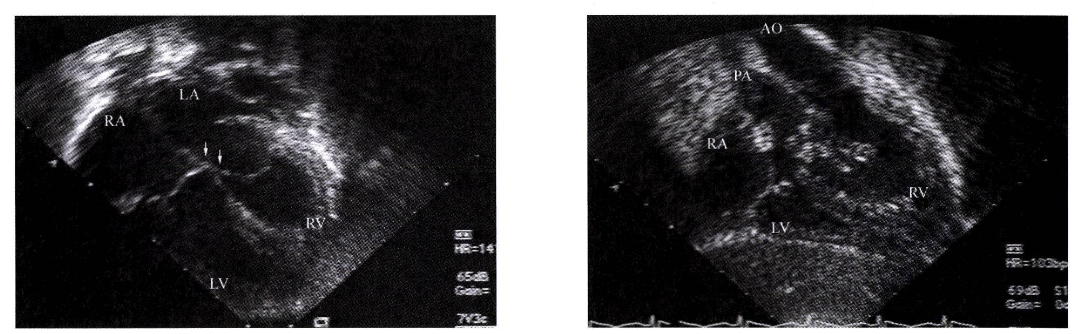

엡스타인 기형 (Ebstein anomaly)

정의: 삼첨판막이 정상보다 우심실 아래쪽에 부착되어있는 심기형

(RV의 RA 화, functional TR발생)

증상: 삼첨판의 전위 정도, TR의 정도, LVOT 의 정도에 따라 다양

심초음파: 진단